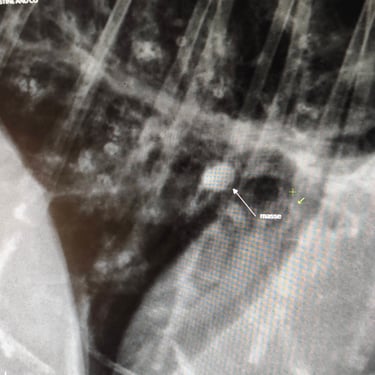

A sa prise en charge, des difficultés à respirer sont constatées . Les examens révèlent un épanchement, ainsi qu'une masse, sans certitude qu'il s'agisse de métastase. Un traitement est en cours et des examens complémentaires seront nécessaires.